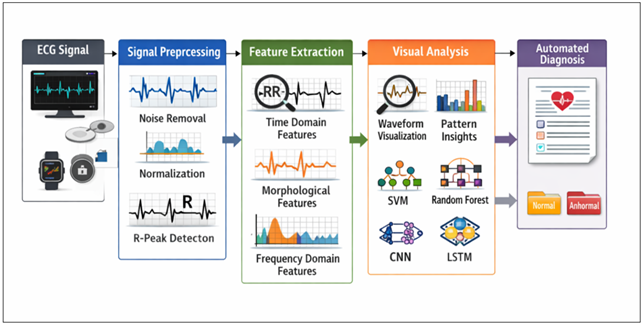

Figure 1 ECG Signal Processing and Machine Learning-Based Automated Cardiac Diagnosis Framework

Figure 1 shows the workflow of automated ECG analysis. Raw ECG signals undergo preprocessing including noise removal, normalization, and R-peak detection. Extracted time, morphological, and frequency features are analyzed using machine learning models (SVM, Random Forest, CNN, LSTM) to enable visual interpretation and automated classification of normal or abnormal cardiac conditions.